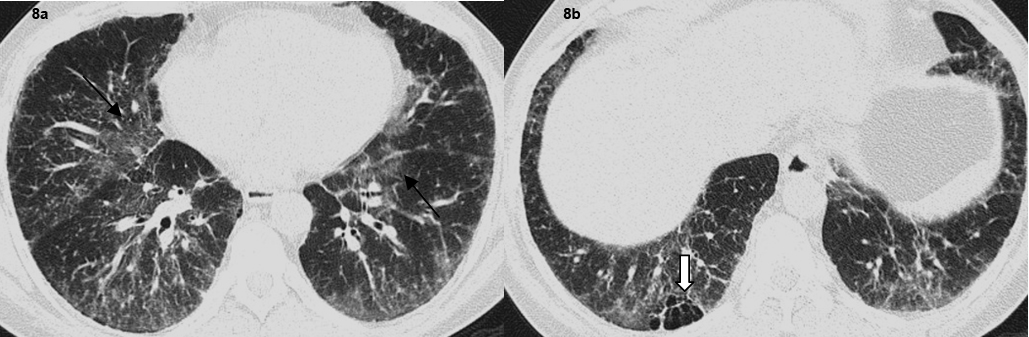

Axial high resolution CT images show (a) patchy ground glass opacification in both lungs (arrows). (b) Focal air trapping seen in right lower lobe (Bold arrow).

A total of 32 patients had lung parenchymal lesions excluding end stage lung disease [Table/Fig-5]. The lung parenchymal findings were classified as being typical or atypical. The most common typical finding seen in 26 patients was micronodular opacities (1-3 mm in size) in a perilymphatic distribution. Perilymphatic distribution included nodules in the peribronchovascular distribution, subpleural regions and nodules along the interlobular septum. Perilymphatic distribution was most commonly appreciated in the parahilar regions and was seen as thickening and nodularity of the peribronchovascular interstitium and in the subpleural locations adjacent to the fissures [Table/Fig-6]. Areas of coalescing of the micronodules into larger nodules of varying sizes were seen in most cases [Table/Fig-7]. Atypical findings were noted in six patients. These atypical findings included patchy ground glass opacities [Table/Fig-8], focal consolidations and confluent conglomerate opacities [Table/Fig-9]. Findings of mosaic attenuation and air trapping were seen in three patients. Predominant involvement of the upper and middle zones was seen in 31 patients. In nine patients, the lesions were found involving both lungs in a diffuse manner [Table/Fig-10,11].

Atypical lung parenchymal lesions were noted in a subset of patients 15% (n=06). These atypical lesions consisted of large pulmonary nodules and masses, patchy air space consolidations, patchy ground glass opacities and areas of air trapping and mosaic attenuation. These opacities represent confluent and coalescing nodules in the interstitium or the acini of the lung parenchyma and are seen in 10 to 40% of patients and are often superimposed on the background of the interstitial nodules [1,13,16]. Air trapping is a non-specific finding which may be seen in a number of patients. Mosaic attenuation pattern indicates small airway involvement by granulomas or fibrosis [17,18].